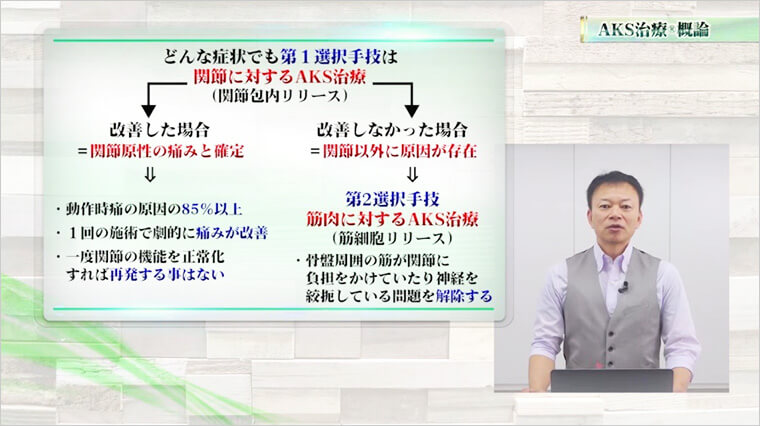

①まずは関節を施術。ほとんどの痛みはこれだけで消える

②取りきれない症状があれば筋細胞リリースで対応

①まずは関節を施術。ほとんどの痛みはこれだけで消える

②取りきれない症状があれば筋細胞リリースで対応